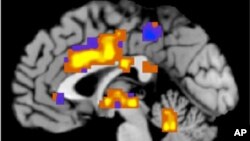

پژوهش: ویتامین دی ممکن است آلزایمر را به تاخیر بیاندازد

در حالی که انتظار می رود بیماری آلزایمر، نوع شایع زوال عقل (دمانس)، طی ۵۰ سال آینده گریبانگیر سالمندان در سراسر جهان شود، پژوهشگران در مورد ویتامین D و تاثیر آن در کند ساختن شروع آن، به مطالعه پرداخته اند.

در گزارشی که در نشریه انجمن پزشکی آمریکا منتشر شده است گفته می شود پژوهشگران متوجه شده اند سطوح پایین ویتامین D ممکن است به زوال عقل و آلزایمر، یکی از شایع ترین شکل های دمانس، ارتباط داشته باشد.